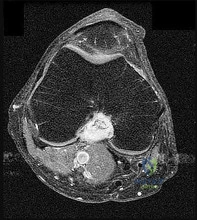

Question 2:

Which of the following surgical approaches is most appropriate for a posteromedial tibial plateau fracture?

Correct Answer: Posteromedial approach

Explanation:

Posteromedial shear fractures of the tibial plateau require buttress plating on the posteromedial surface. A posteromedial approach interval is between the medial head of the gastrocnemius and the pes anserinus.